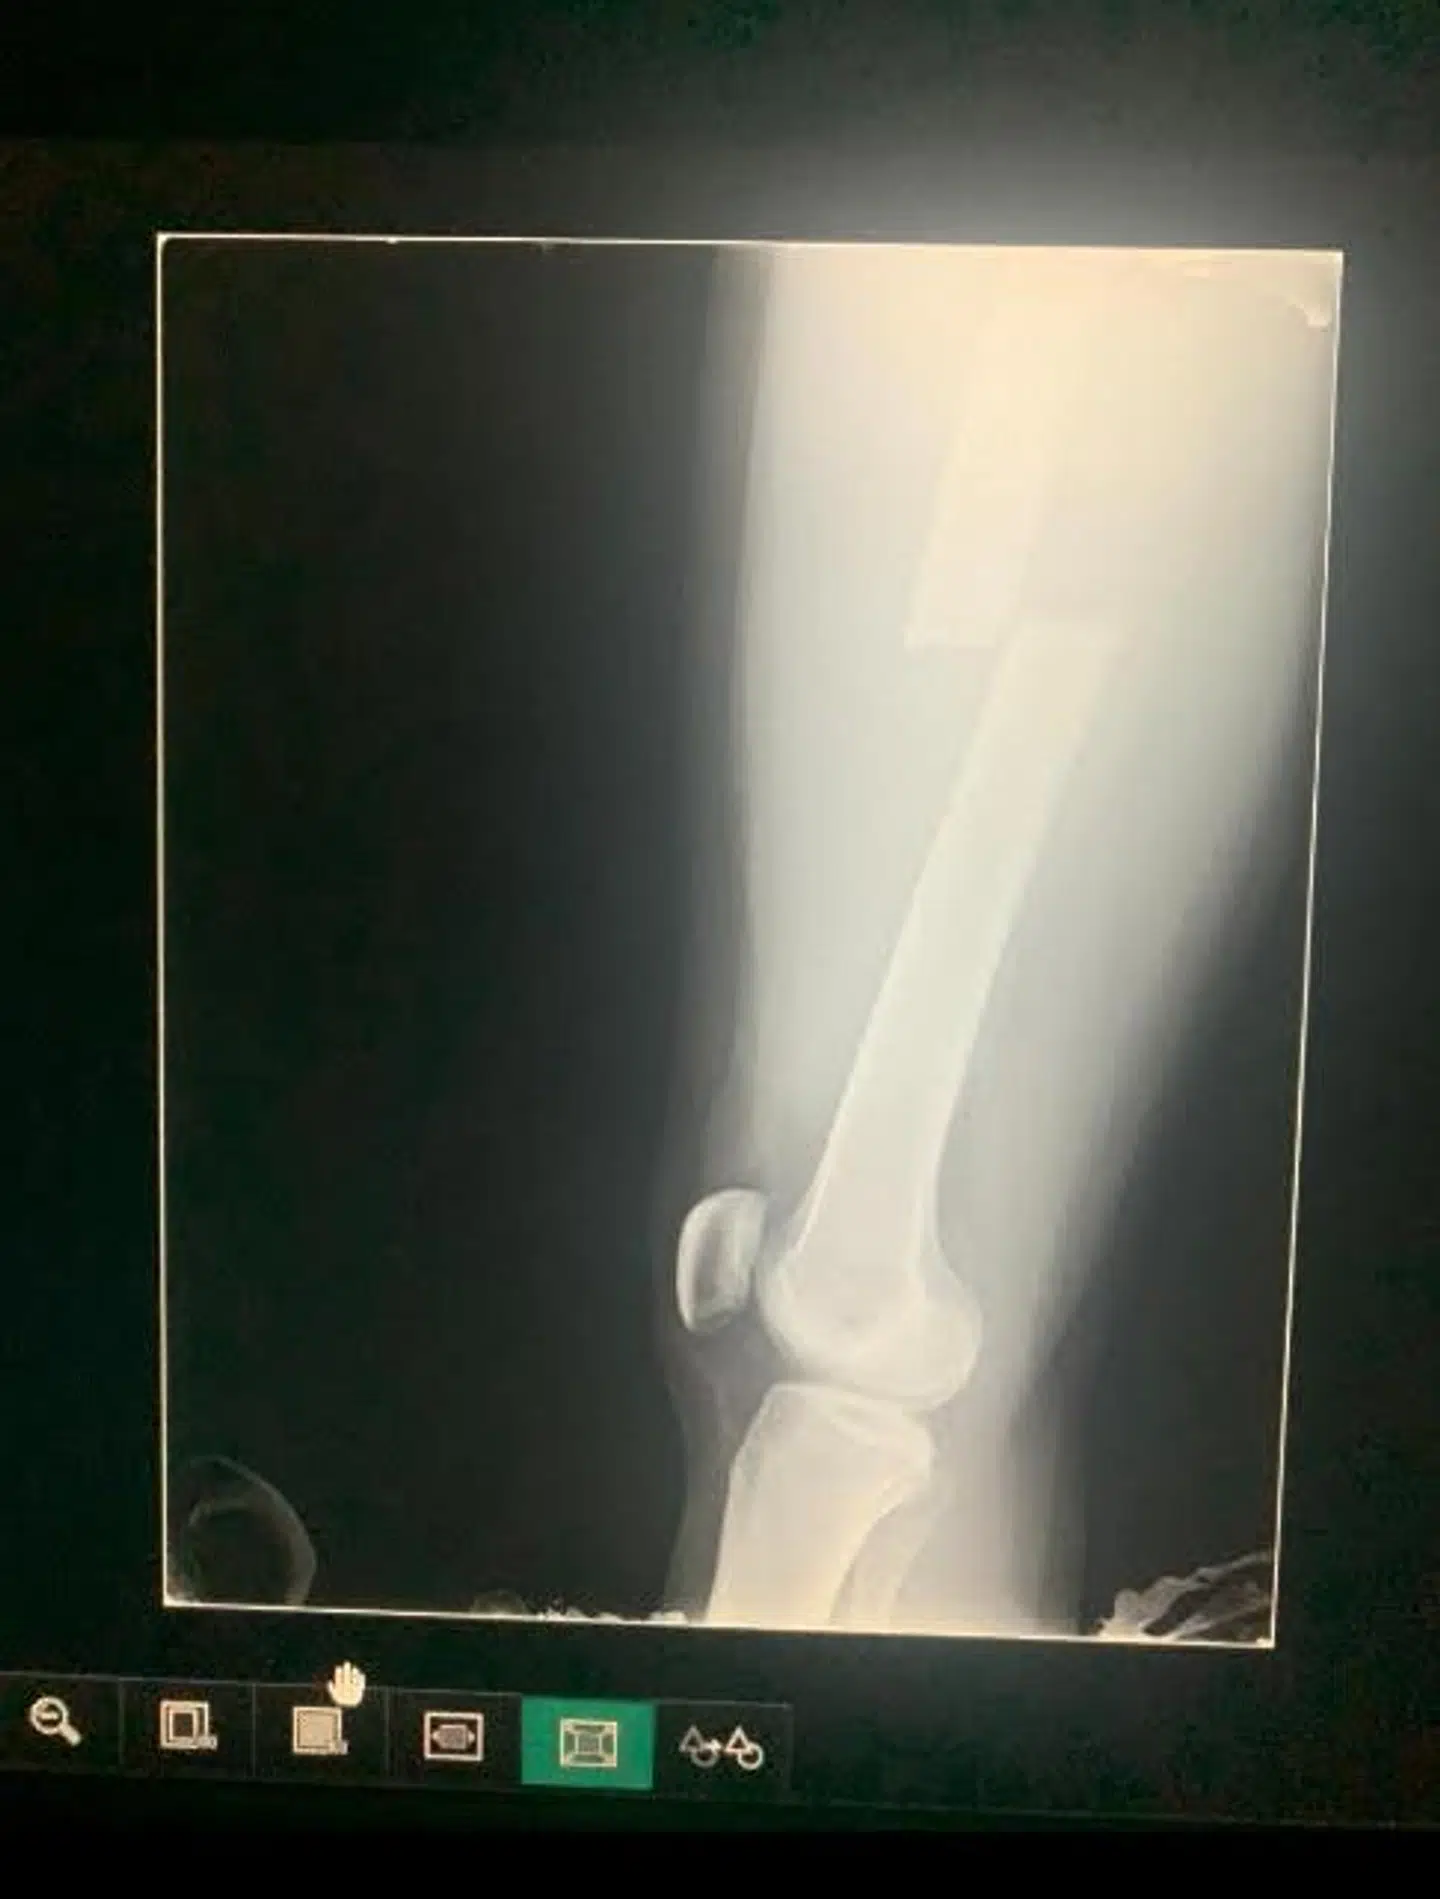

Så hun hopper af, og så lyder der et stort knæk. Hendes lårbensknogle brækker.

Først viste den stang, hun skulle have indopereret, sig at have den forkerte størrelse – efter hun var blevet bedøvet.

Da stangen så var skaffet, og operationen kunne gå i gang, var hun denne gang ikke blevet bedøvet nok. Så hun vågnede op under operationen, til hvad der for hende lød som en byggeplads, og måtte bede om mere medicin.